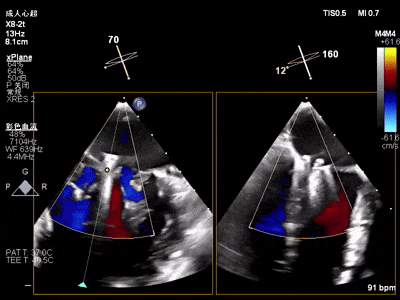

术中超声(关键步骤)

术前心超

混合性MR,P2脱垂连枷(脱垂范围15mm,连枷间距4mm),腱索断裂

新分型:ACA型,反流2区及两侧,MR 4+,VC:3×14mm

A2:24mm,P2:17mm,AP:38mm,MVA约5.7cm²

术中超声要点: